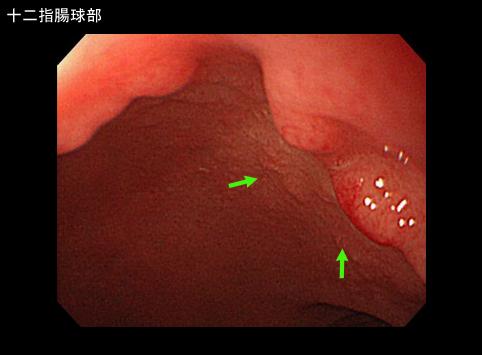

A case of ectopic gastric mucosa which was recognized in the duodenal bulb.

Tumor-like lesions/ectopic mucosa

Duodenum/First portion, bulb

Endoscopy

1 - 9